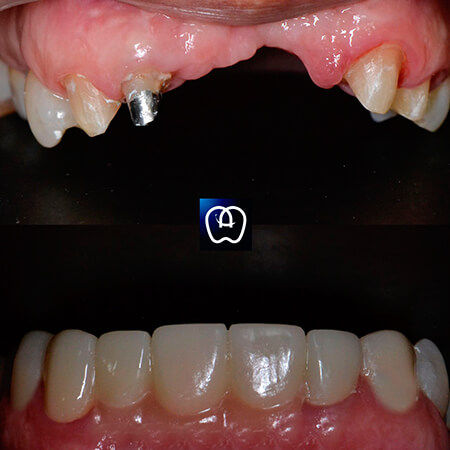

Galería de antes y después

Las especialidades de Álvarez & Arráez Odontología son: Odontólogo, Implantes dentales, Odontología láser, Odontología estética, Rehabilitación oral, Periodoncia, Endodoncia, Odontopediatra, Ortodoncia.